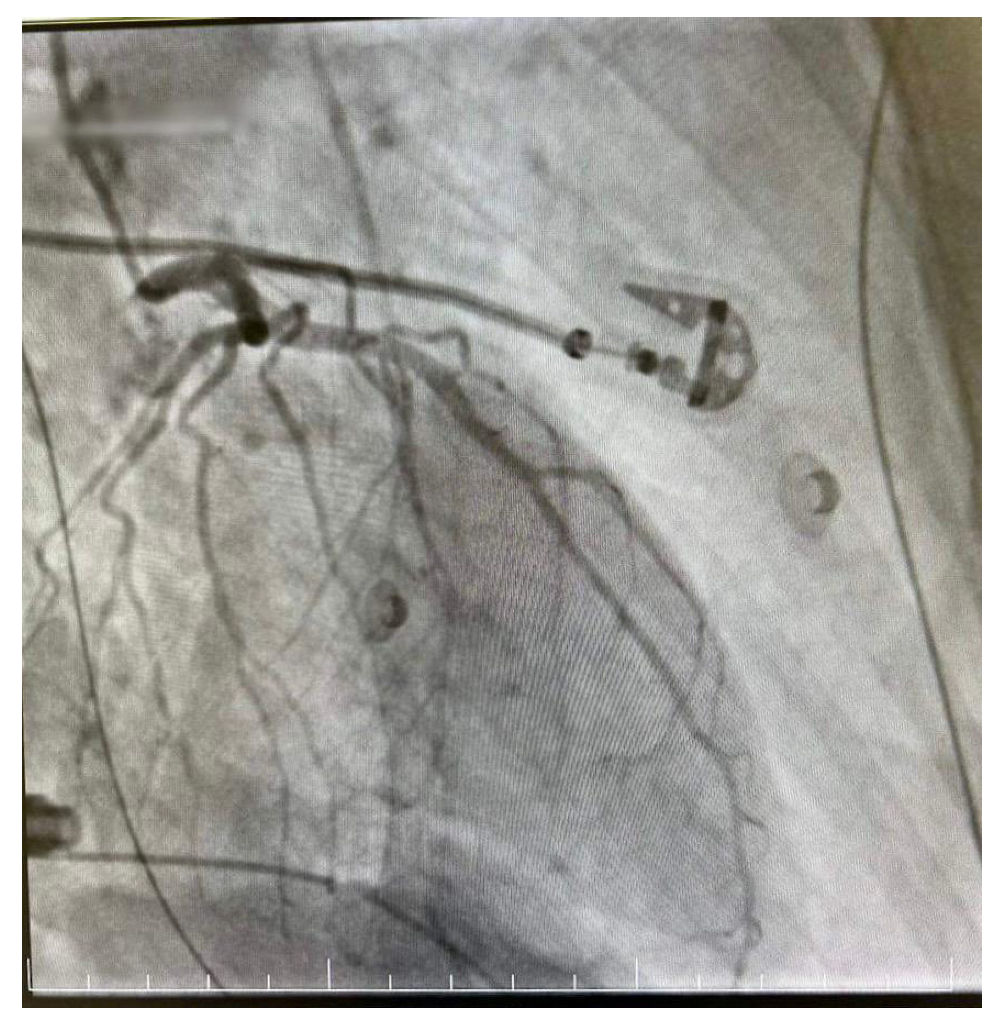

The decision was made to perform a coronarography, which showed no signs of acute or chronic coronary obstruction (Figure 5 and Figure 6). The patient was put on a continuous infusion of 0.01 micrograms/kg/min of noradrenaline and 1.8 mcg/kg/min of dobutamine with 40 mg of enoxaparin given the next day. She remained intubated for 48 h and the improvement of her hemodynamic status allowed the discontinuation of the inotropic medication the following day. After the steady improvement of the respiratory and cardiac functions, the patient’s clinical status allowed extubation with spontaneous breathing. The patient was started on the standard therapy for cardiac insufficiency, consisting of beta blockers, antiarrhythmic therapy, Angiotensin-converting enzyme (ACE) inhibitors and levosimendan. The following echocardiogram showed slow but steady improvement in the cardiac function. She was discharged from intensive care on day 6 and from the hospital on day 10. The echocardiogram conducted on the day she was discharged from the ICU revealed an EF of 25%, with akinesia of the ventricular apex and medio/apical segments, with no right ventricular dilatation and mild mitral regurgitation. On day 9 after HIPEC, the echocardiogram revealed an EF of 30–35% with hypokinesis of the apex and middle-to-apical segments of the heart. The patient did not complain of angina or dyspnea and tolerated lying in the supine position. She was discharged from the hospital on a combination of beta blockers, antiarrhythmic medication and ACE inhibitors, with a follow-up echocardiogram after one month.

Figure 6.

Right dominant coronary system without significant angiographic lesions.